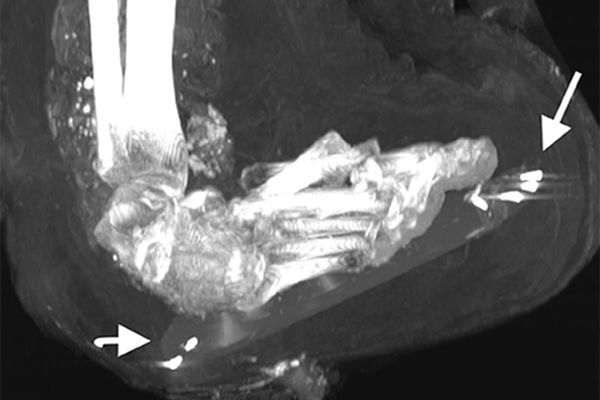

Исследователи обнаружили у Аменхотепа множество травм, но все они оказались посмертными: переломы шеи и позвоночника, вывихи и переломы рук, перелом лобковой кости. На одной из рук отсутствуют два пальца, они уложены в районе живота мумии. По всей видимости, мумия пострадала от рук расхитителей гробниц.

При повторном захоронении мумию явно пытались «отремонтировать» — пропитанные смолой бинты фиксировали оторвавшуюся из-за перелома шейных позвонков голову, прикрывали повреждения брюшной полости. Сломанным и вывихнутым конечностям придано подходящее положение. Ступни зафиксированы с помощью деревянных дощечек.